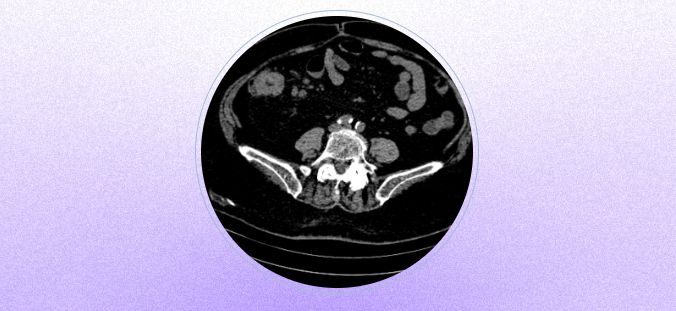

完善胸腹部CT

肠镜

PET/CT肿瘤全身断层显像等

一系列检查

副主任医师胡德升得出明确结论

升结肠癌

胡德升面对着三个棘手问题

问题一:

重度的腹型肥胖

妈妈BMI达到40上下

腹围120cm

问题二:

左肾切除

右肾在手术区域下方

问题三:

当年腹壁侵袭性

纤维瘤手术

放置的补片

极大影响手术入路